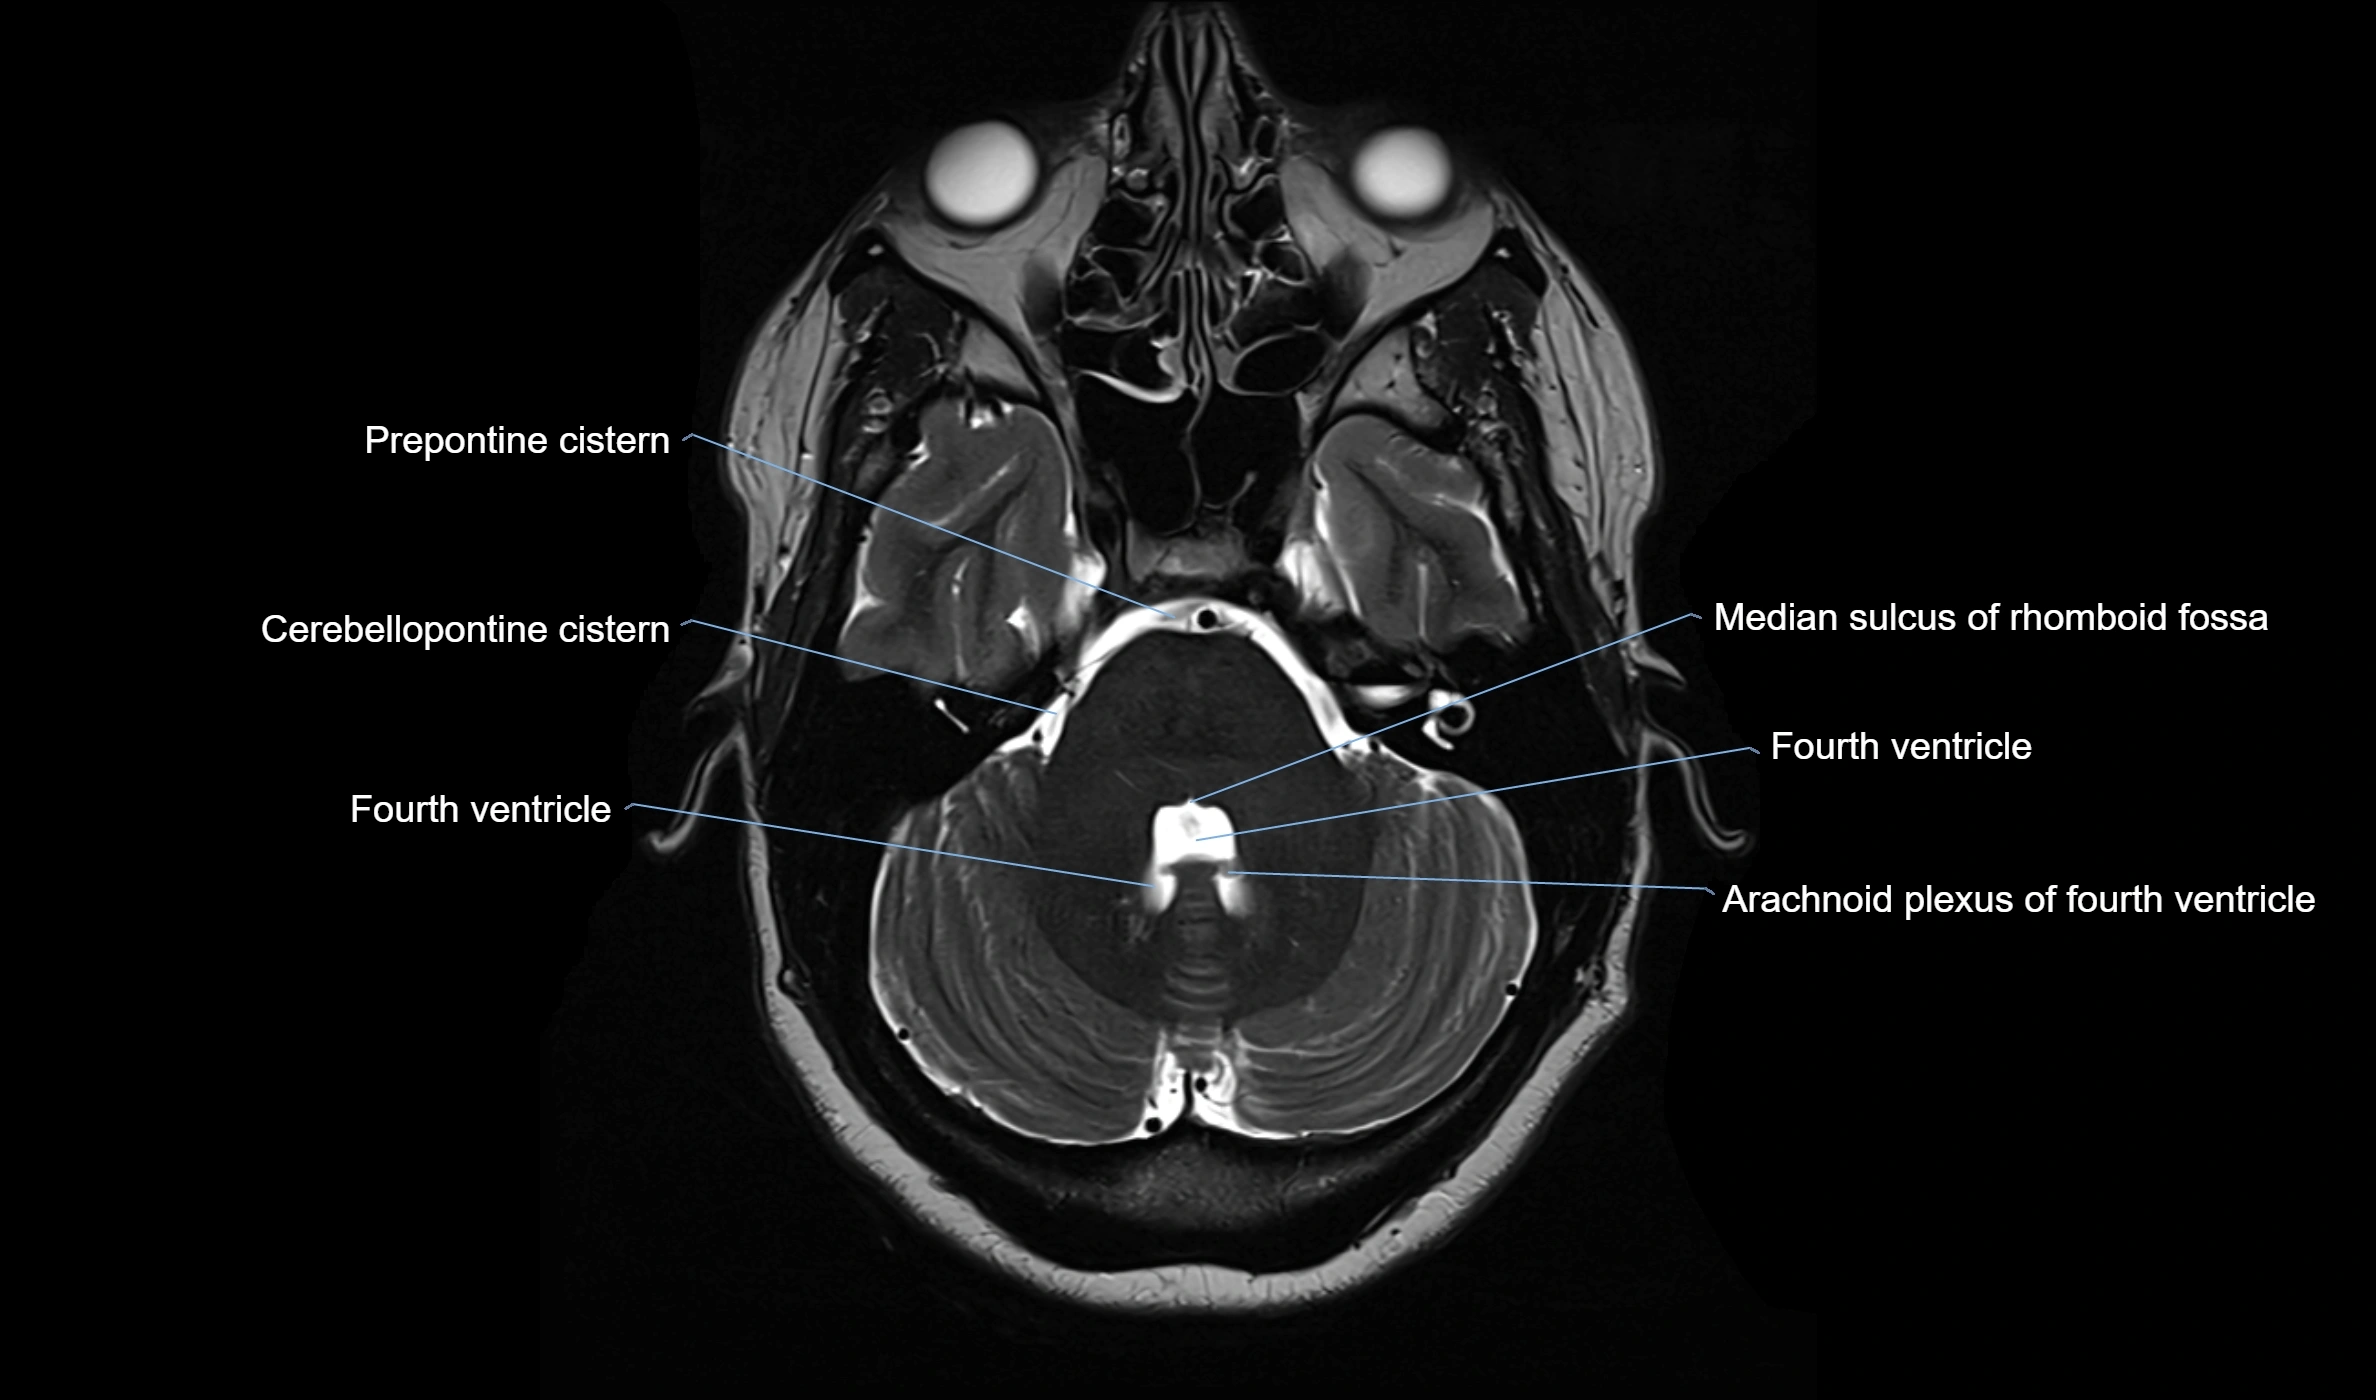

MRI images

image